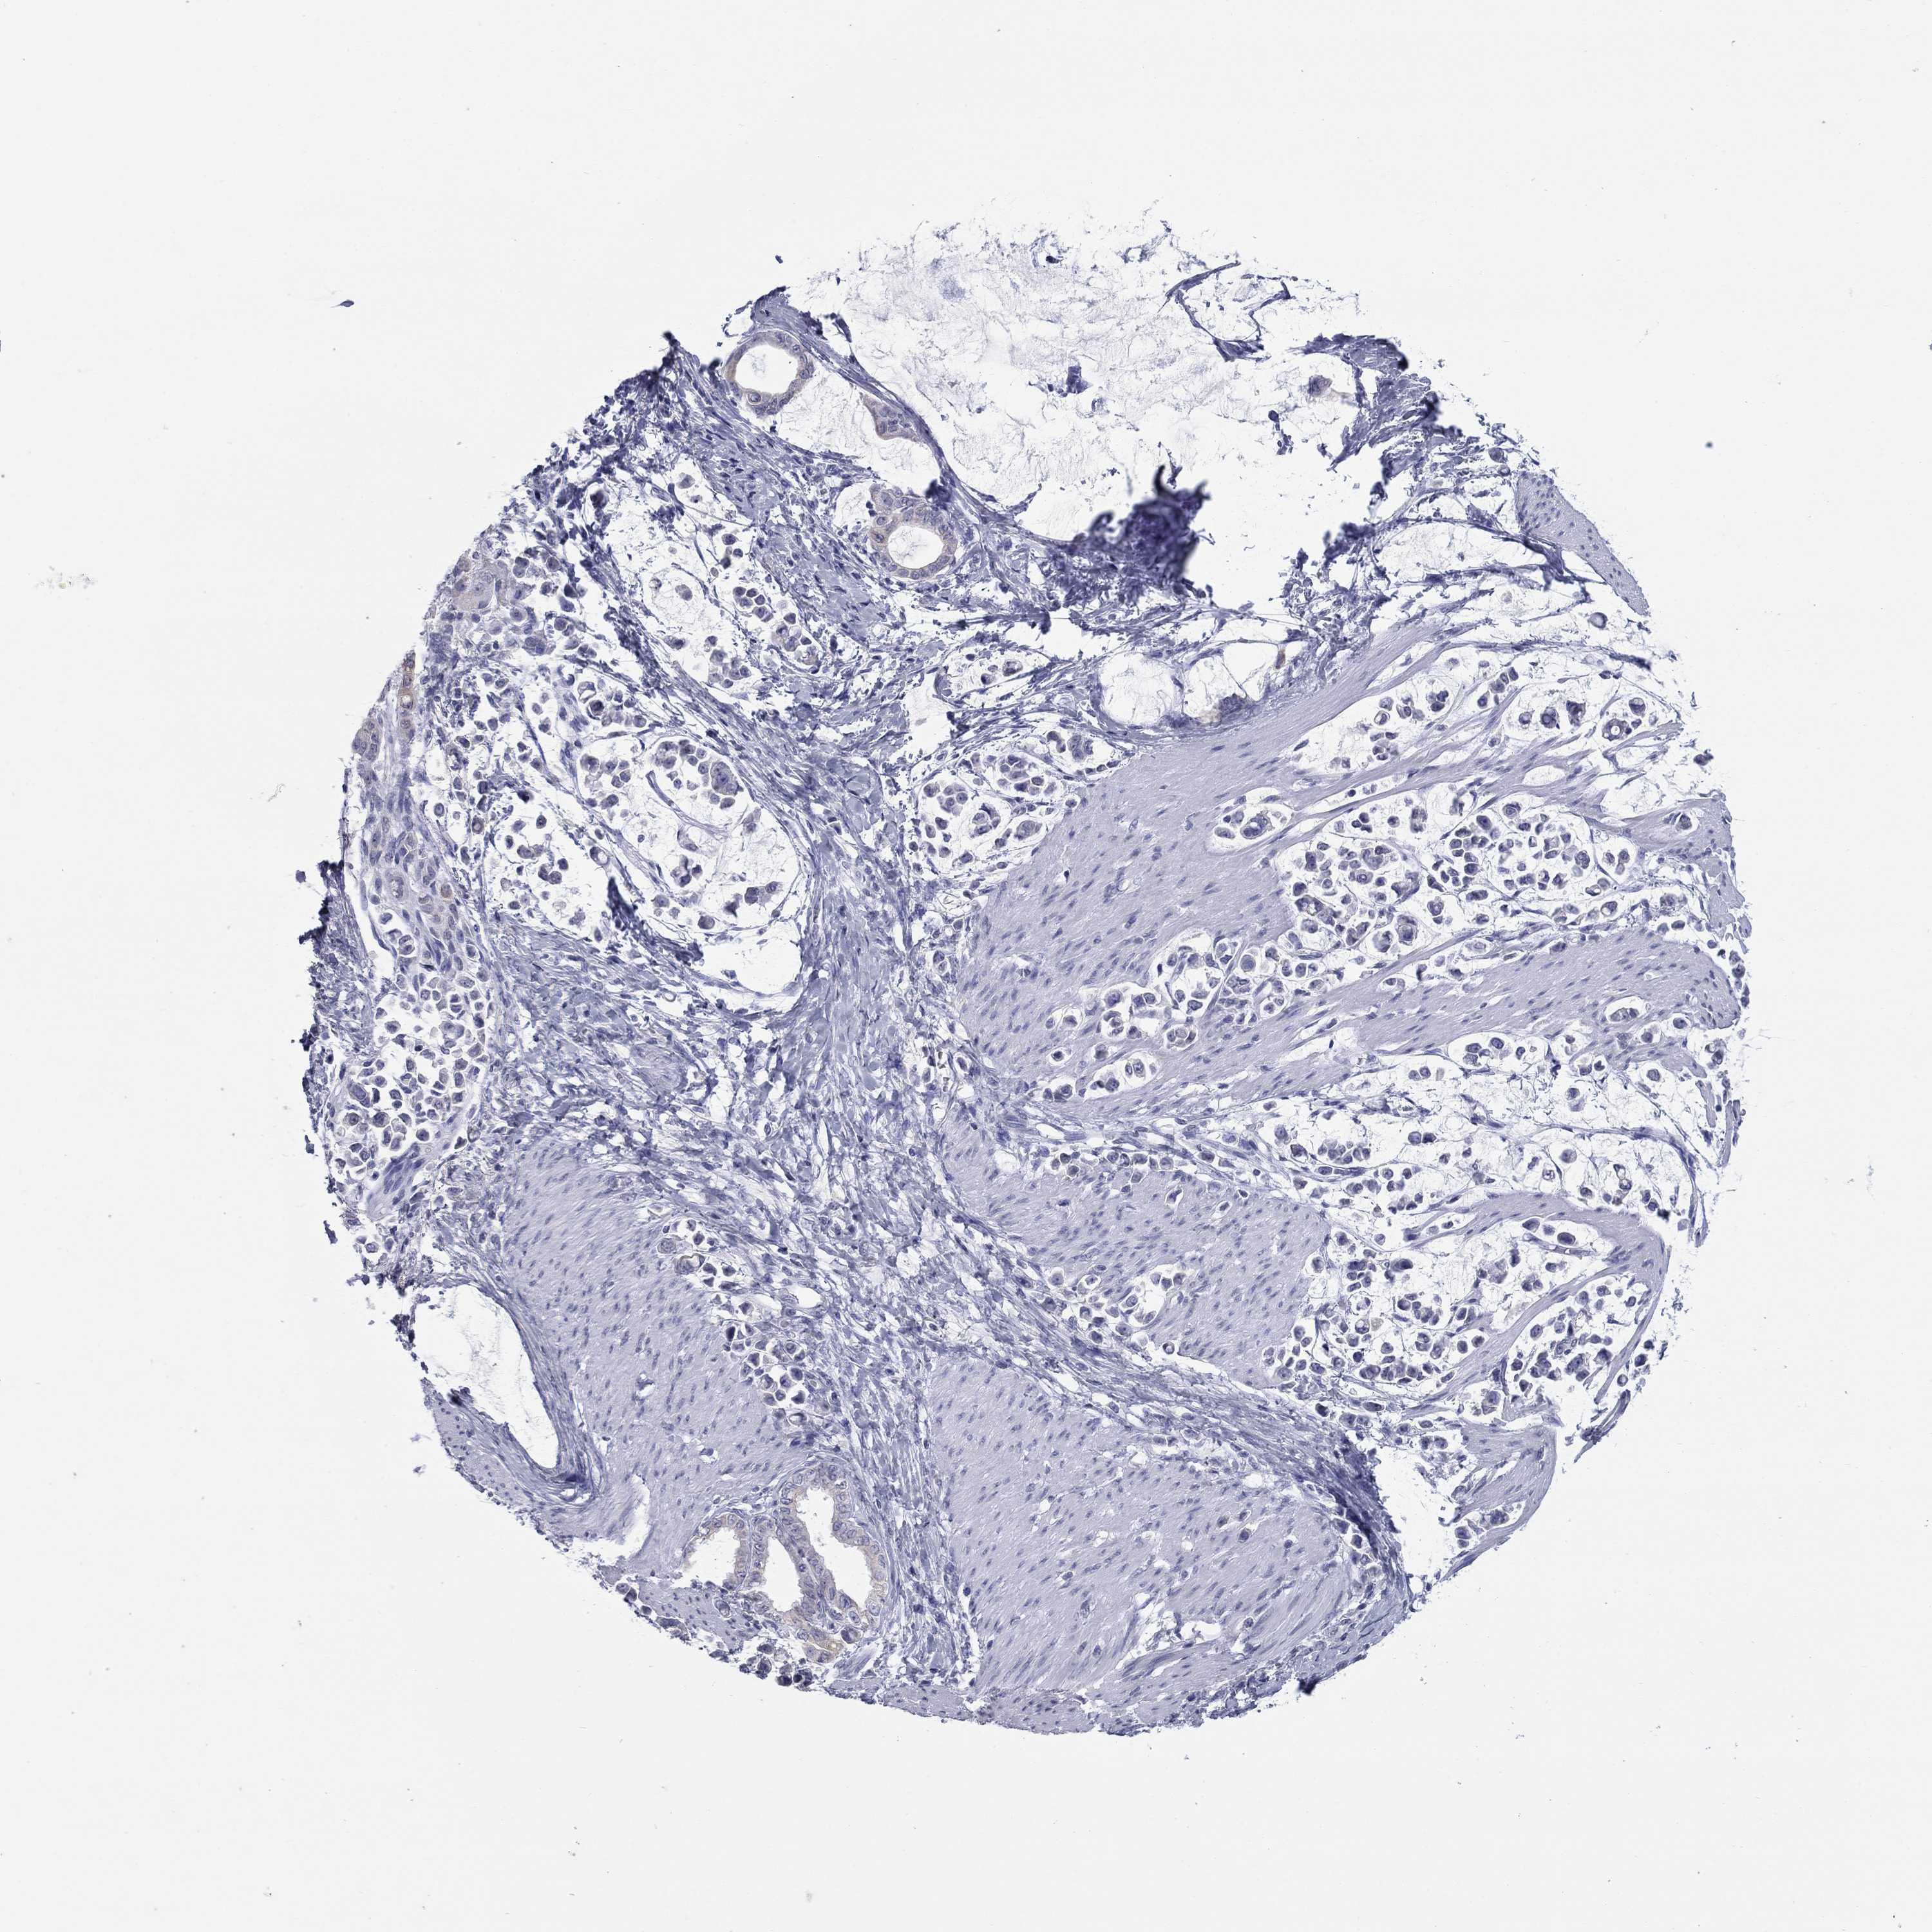

STOMACH CANCER - Protein expressioni

A mouse-over function shows sample information and annotation data. Click on an image to view it in a full screen mode. Samples can be filtered based on level of antibody staining by selecting one or several of the following categories: high, medium, low and not detected. The assay and annotation is described here.

Note that samples used for immunohistochemistry by the Human Protein Atlas do not correspond to samples in the TCGA dataset.

Antibody stainingi

Antibody staining in the annotated cell types in the current human tissue is reported as not detected, low, medium, or high, based on conventional immunohistochemistry profiling in selected tissues. This score is based on the combination of the staining intensity and fraction of stained cells.

Each image is clickable and will lead to virtual microscopy that enables deeper exploration of all samples and also displays staining intensity scores, fraction scores and subcellular localization as well as patient and tissue information for each sample.

Antibody HPA019367

Antibody HPA076201

Staining

High

Medium

Low

Not detected

Intensity

Strong

Moderate

Weak

Negative

Quantity

>75%

75%-25%

<25%

None

Location

Nuclear

Cytoplasmic/membranous

Cytoplasmic/membranous,nuclear

Adenocarcinoma, NOS

Adenocarcinoma, High grade